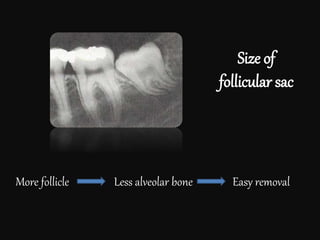

Size of

follicular sac

More follicle Less alveolar bone Easy removal